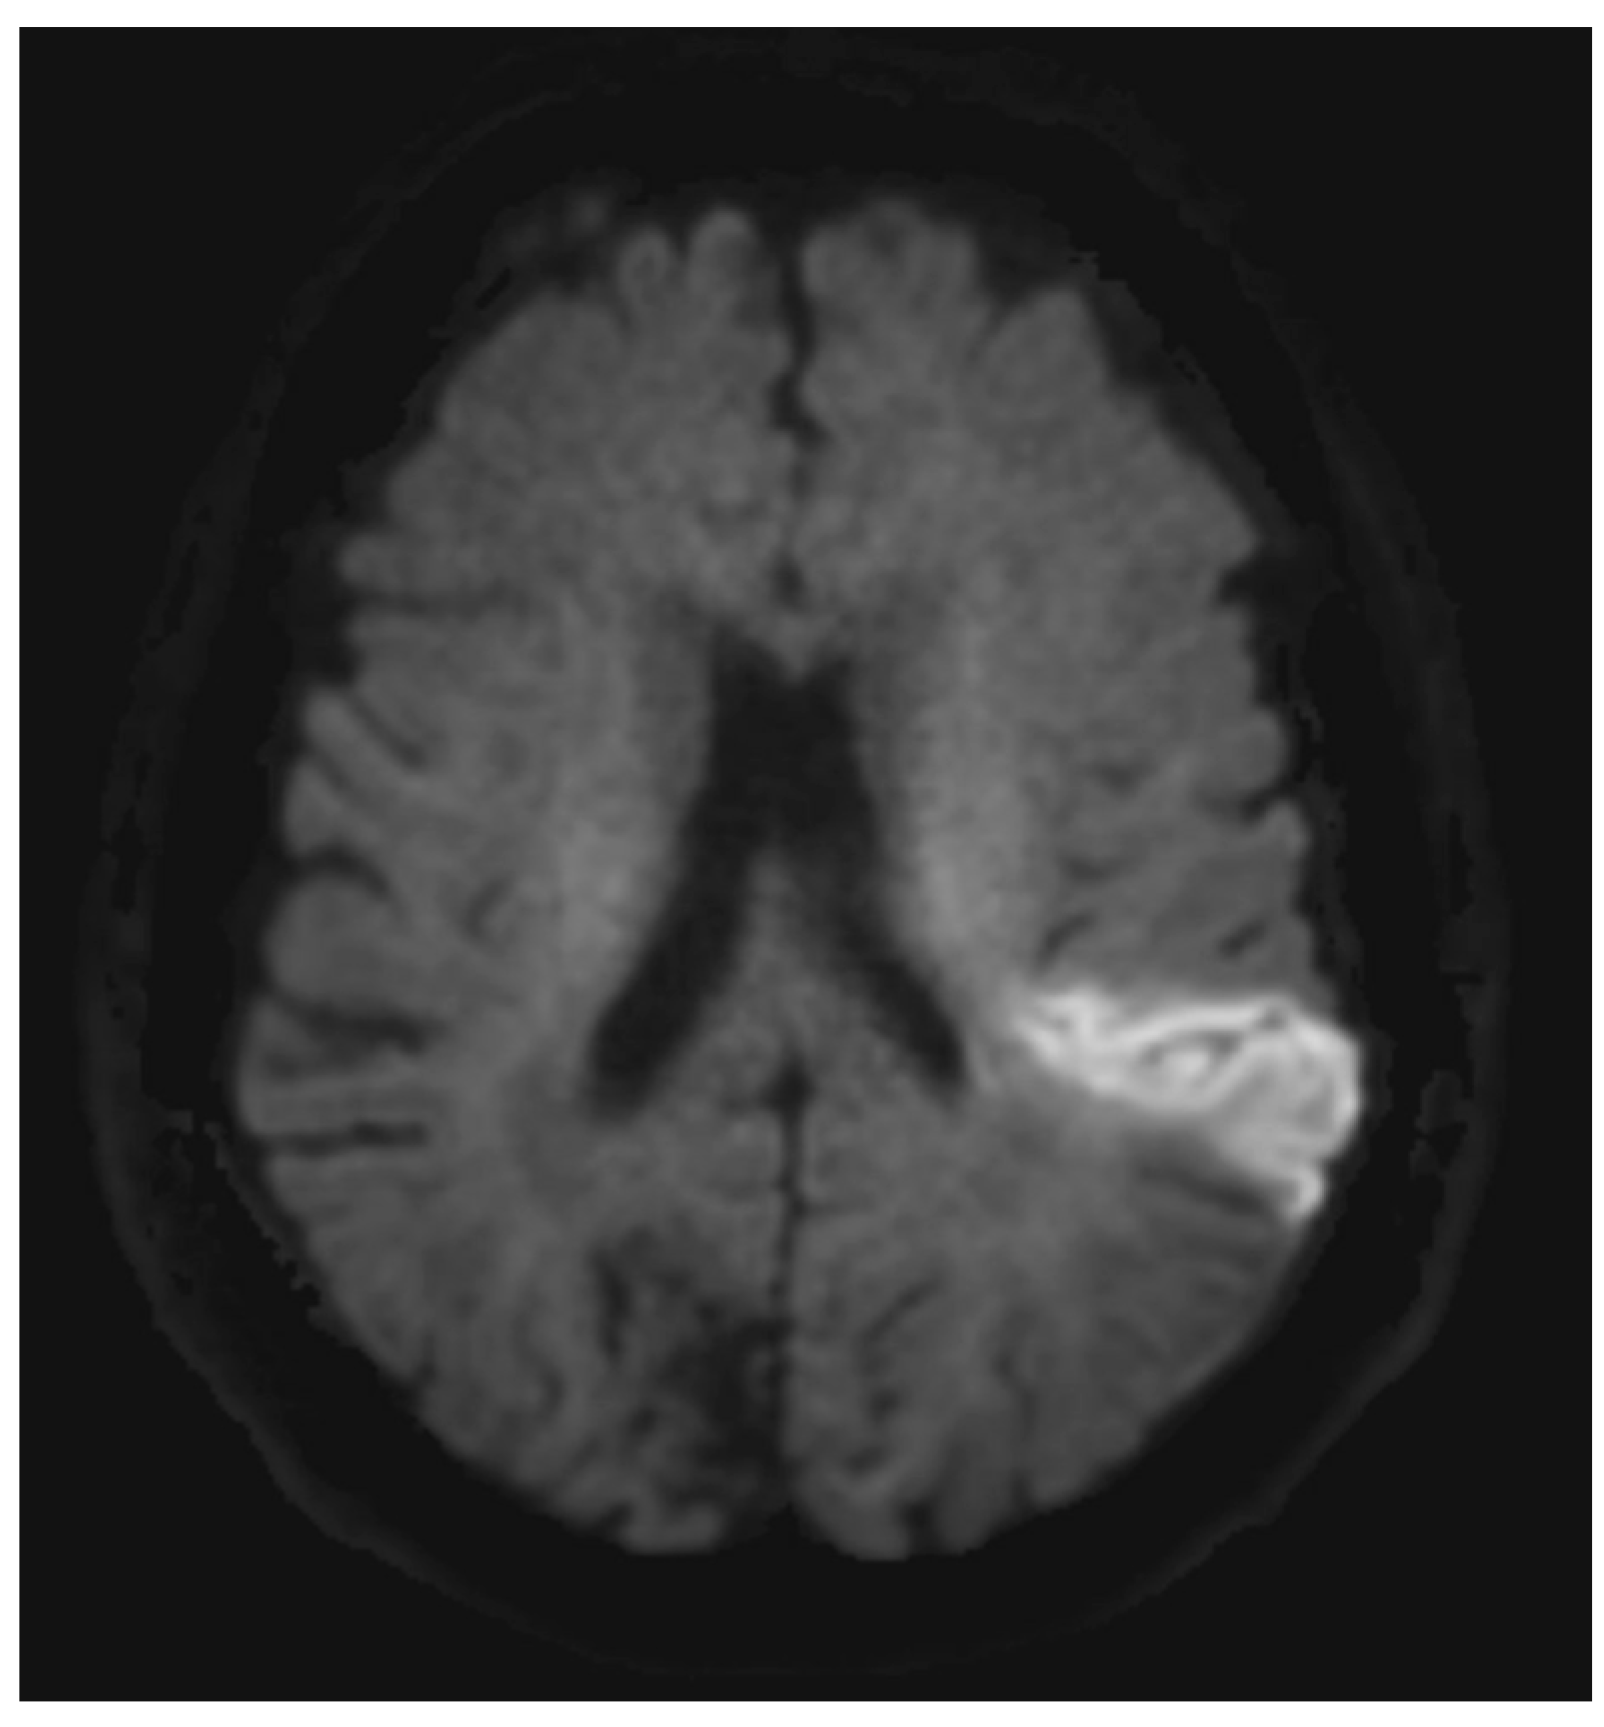

AF-related IS often presents with a distinct radiologic pattern indicating embolic stroke, i.e., a typical wedge-shaped cortical-subcortical infarct [38] (Figure 1). AF-related IS can affect any vascular territory, and multiple vascular territories can be affected [39].

Figure 1.

Diffusion-weighted imaging (DWI). Case of cardioembolic infarct in left hemisphere (bright area).